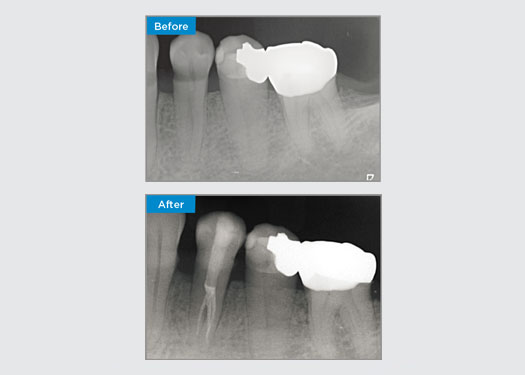

Le patient s’est présenté avec une pulpite irréversible sur la dent 46. Sur la radiographie préopératoire, la dent 46 présente une racine distale supplémentaire (morphologie de la dent Radix Entromolaris). Un balayage CBCT a confirmé la présence d’une racine DL avec une courbure radiculaire sévère. Une sélection minutieuse des limes est essentielle pour cette racine DB délicate.

Dr Jack Lin, Endodontiste, Sydney, NSW Australie